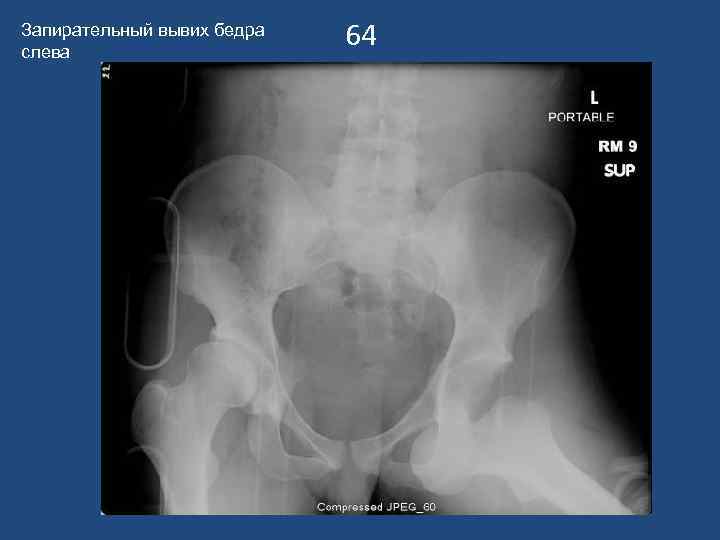

Запирательный вывих бедра слева 64